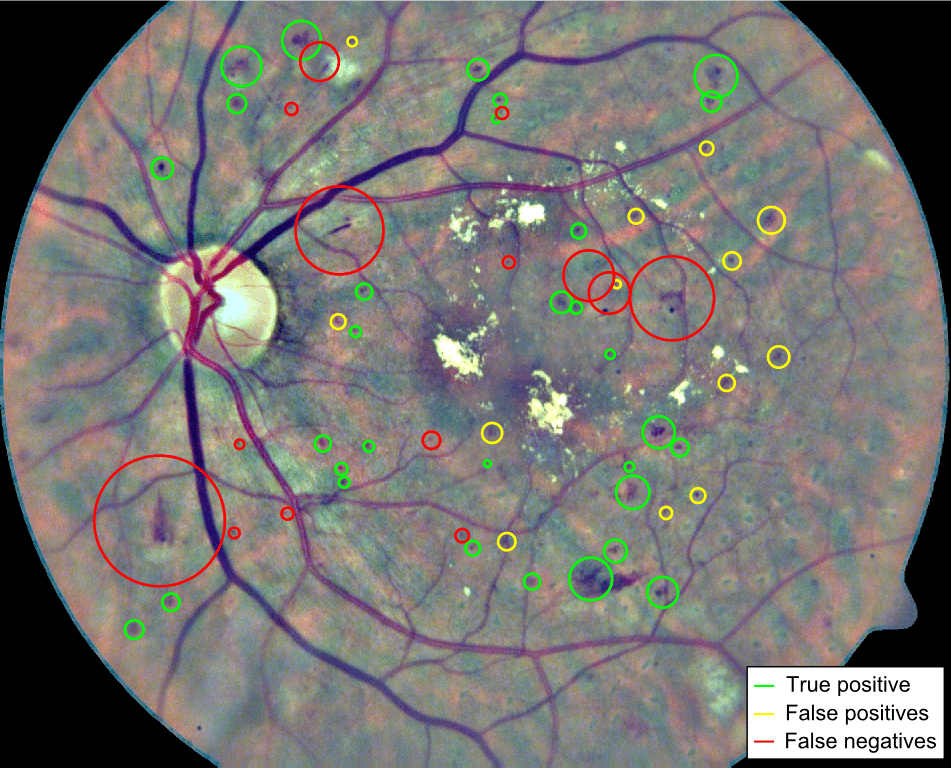

Finally, qualitative results for a randomly selected image in the DIARETDB1 test set are depicted in Figure 10. Green circles are detected lesions according to the ground truth labeling provided in the data set, while yellow circles correspond to lesions detected by our method but that are not labeled in the ground truth. Finally, red circles surround the lesions that were manually annotated as true lesions but were ignored by the method. Qualitatively, many of the yellow circles appear to be microaneurysms or hemorrhages that were not detected during manual labeling due to their subtle appearance in the original RGB image.